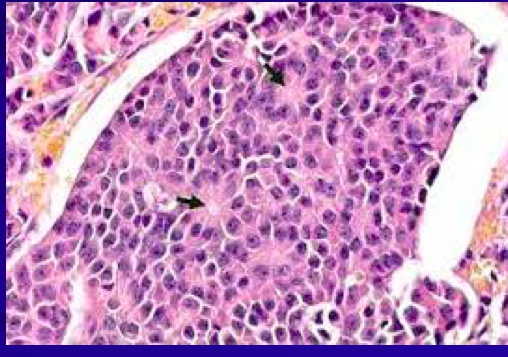

_Are of neuroendocrine origin..

_Histology shows rosettes:..